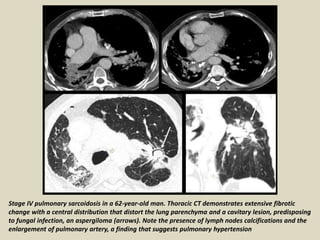

Stage IV pulmonary sarcoidosis in a 62-year-old man. Thoracic CT demonstrates extensive fibrotic

change with a central distribution that distort the lung parenchyma and a cavitary lesion, predisposing

to fungal infection, an aspergiloma (arrows). Note the presence of lymph nodes calcifications and the

enlargement of pulmonary artery, a finding that suggests pulmonary hypertension